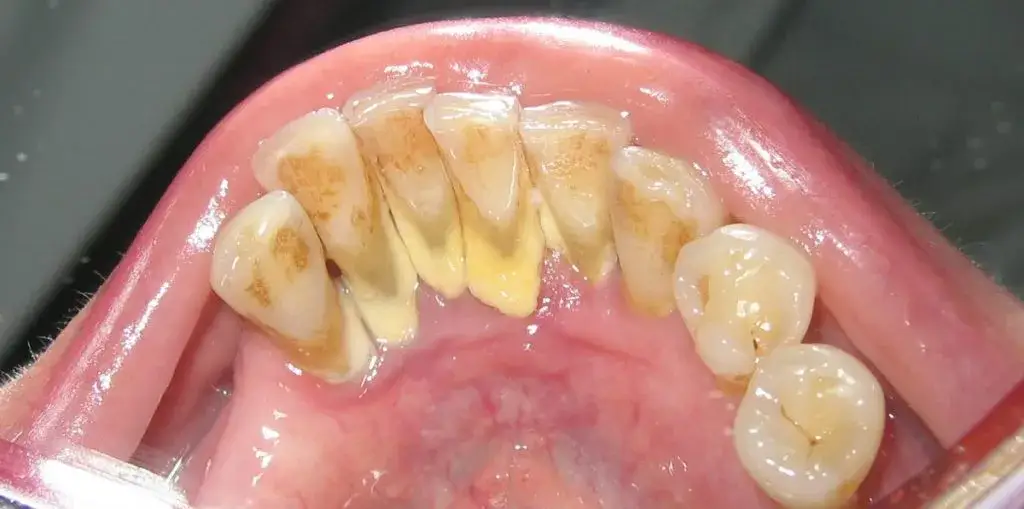

Zrozumienie różnicy między płytką nazębną a kamieniem jest absolutnie kluczowe dla skutecznej profilaktyki. Płytka nazębna to miękki, lepki, bezbarwny biofilm bakteryjny, który nieustannie gromadzi się na powierzchni zębów. Możemy ją usunąć samodzielnie, codziennie szczotkując zęby i używając nici dentystycznej. Kamień nazębny natomiast to już zmineralizowana i utwardzona forma tej płytki. Jest on twardy, często ma żółtawy lub brązowy kolor i, co najważniejsze, nie da się go usunąć zwykłą szczoteczką do zębów czy nicią dentystyczną. Wymaga on interwencji stomatologicznej.

Kamień nazębny ma swoje ulubione miejsca w jamie ustnej są to zazwyczaj obszary, do których trudno dotrzeć podczas codziennego szczotkowania. Najczęściej gromadzi się on na powierzchniach językowych dolnych zębów przednich (siekaczy), w okolicach ujść ślinianek, gdzie ślina jest najbogatsza w sole mineralne. Często znajdziemy go również na powierzchniach policzkowych górnych zębów trzonowych oraz w przestrzeniach międzyzębowych i tuż przy linii dziąseł. To właśnie te trudno dostępne zakamarki wymagają szczególnej uwagi podczas higieny i są pierwszymi punktami, które sprawdzam u moich pacjentów.